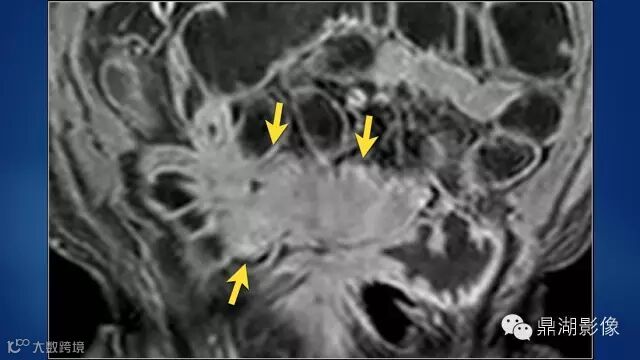

do you know comb sign?

The comb sign refers to the hypervascular appearance of the mesentery in active Crohn disease.

It is the comb sign the most specific sign for crohn's disease.